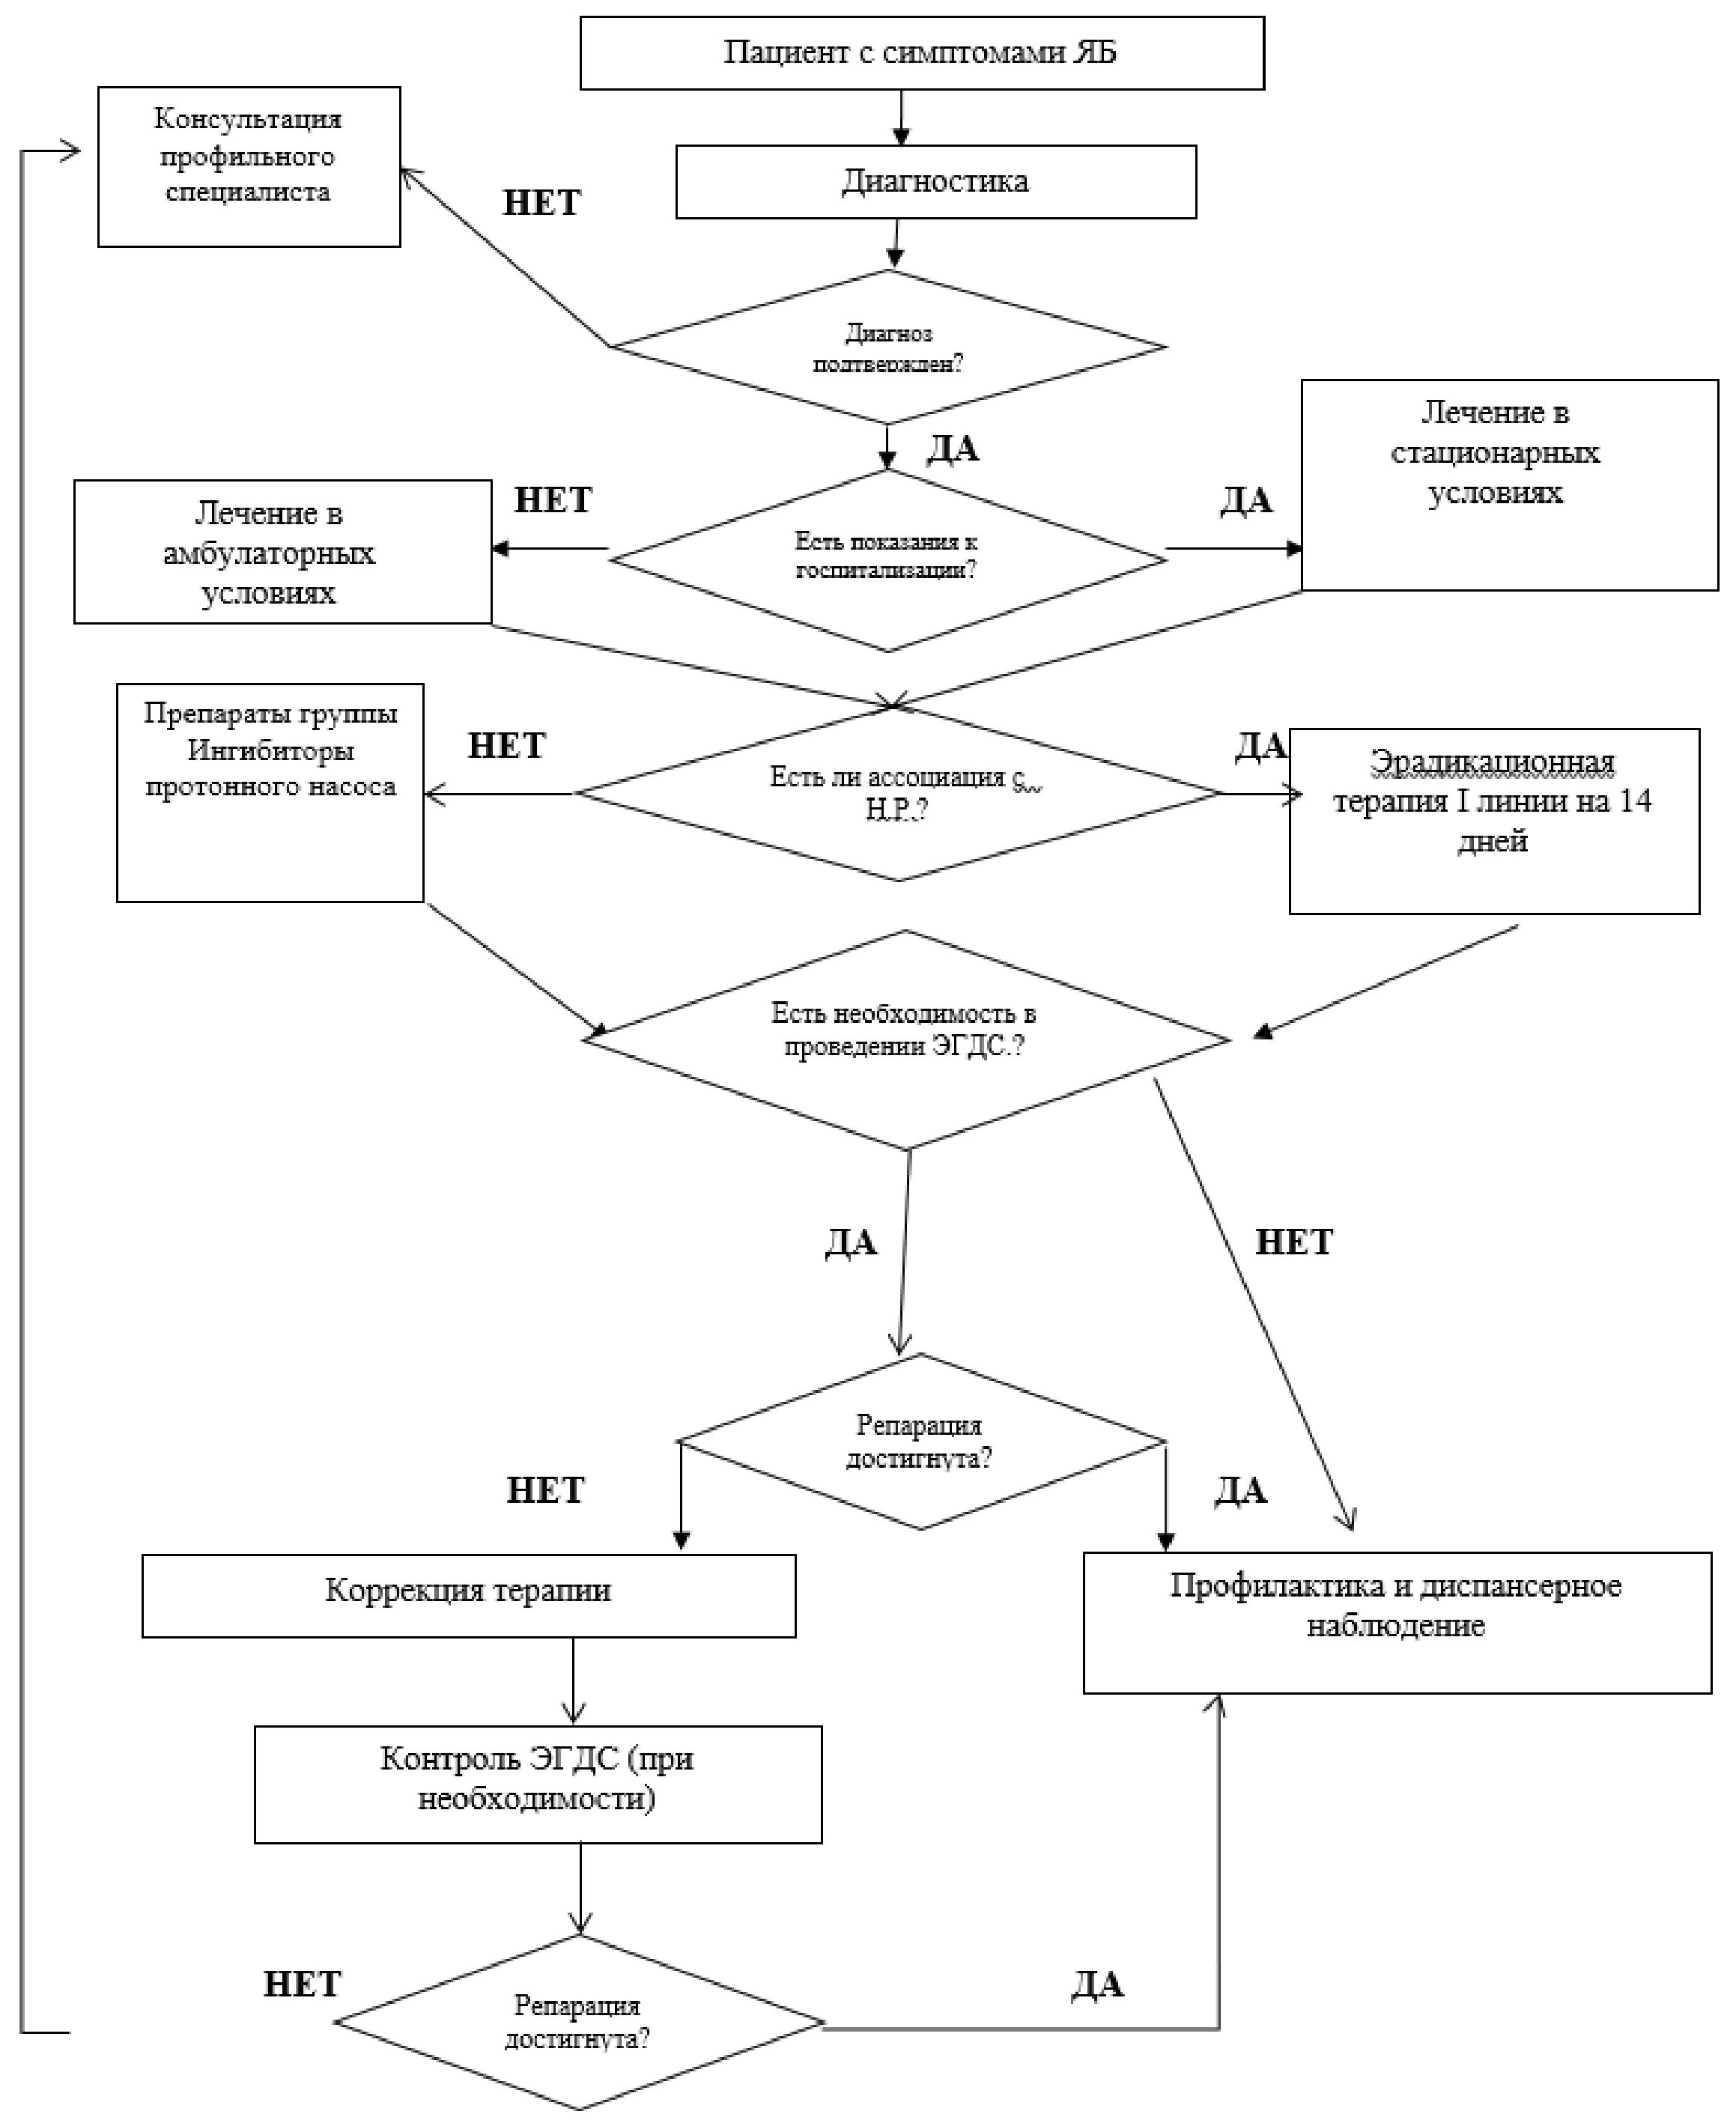

6. Организация оказания медицинской помощи

Медицинская помощь детям с ЯБ может оказываться амбулаторно, в дневном стационаре, стационарно.

Виды медицинской помощи: плановая, неотложная, экстренная.

Дети с впервые выявленной ЯБ в фазе обострения должны пройти обследование и лечение в условиях отделений гастроэнтерологического или педиатрического профиля, при неосложненных язвах - амбулаторно, при наличии выявленных хирургических осложнений - в отделениях хирургического профиля [13].

Комментарии: Длительность пребывания в стационаре определяется индивидуально. Стационарное лечение пациентов с ЯБ в фазе ремиссии, как правило, нецелесообразно.

Дети с неосложнённым течением язвенной болезни подлежат консервативному лечению в амбулаторно-поликлинических условиях.

Дети в стадии ремиссии наблюдаются в амбулаторных условиях.

Детей с язвенной болезнью наблюдает врач-гастроэнтеролог или врач-педиатр, при необходимости осуществляется консультация/лечение врачом - детским хирургом.

Показания для стационарного лечения:

- ЯБ вне зависимости от фазы заболевания при наличии выраженных клинических проявлений обострения (выраженный болевой абдоминальный синдром, диспепсические жалобы); Осложненное и/или рецидивирующее течение ЯБ;

- Сочетание ЯБ с соматической патологией, в том числе желудочно-кишечного тракта;

- Необходимость проведения дифференциальной диагностики с доброкачественными и злокачественными новообразованиями.